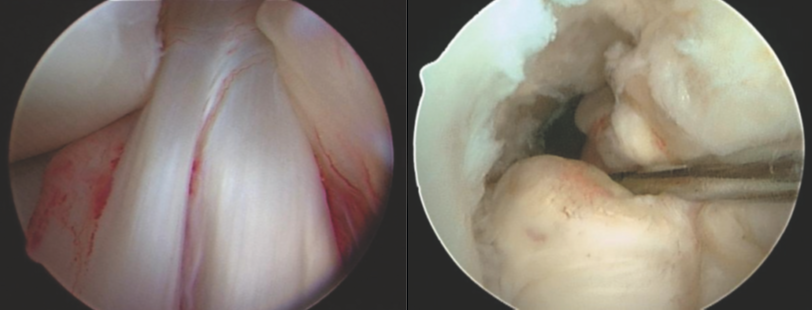

Ligamento Cruzado Anterior

Es uno de los principales ligamentos de rodilla y el principal restrictor del desplazamiento anterior de la rodilla, se lesiona generalmente al cambiar de dirección o girar la rodilla al correr, al saltar y caer de tal forma que hay una torsión de la rodilla.

Las roturas de este ligamento hacen necesaria su reconstrucción artroscópica usando injertos propios (autoinjerto) o injertos externos (aloinjertos) y una recuperación prolongada antes de la reincorporación al deporte.